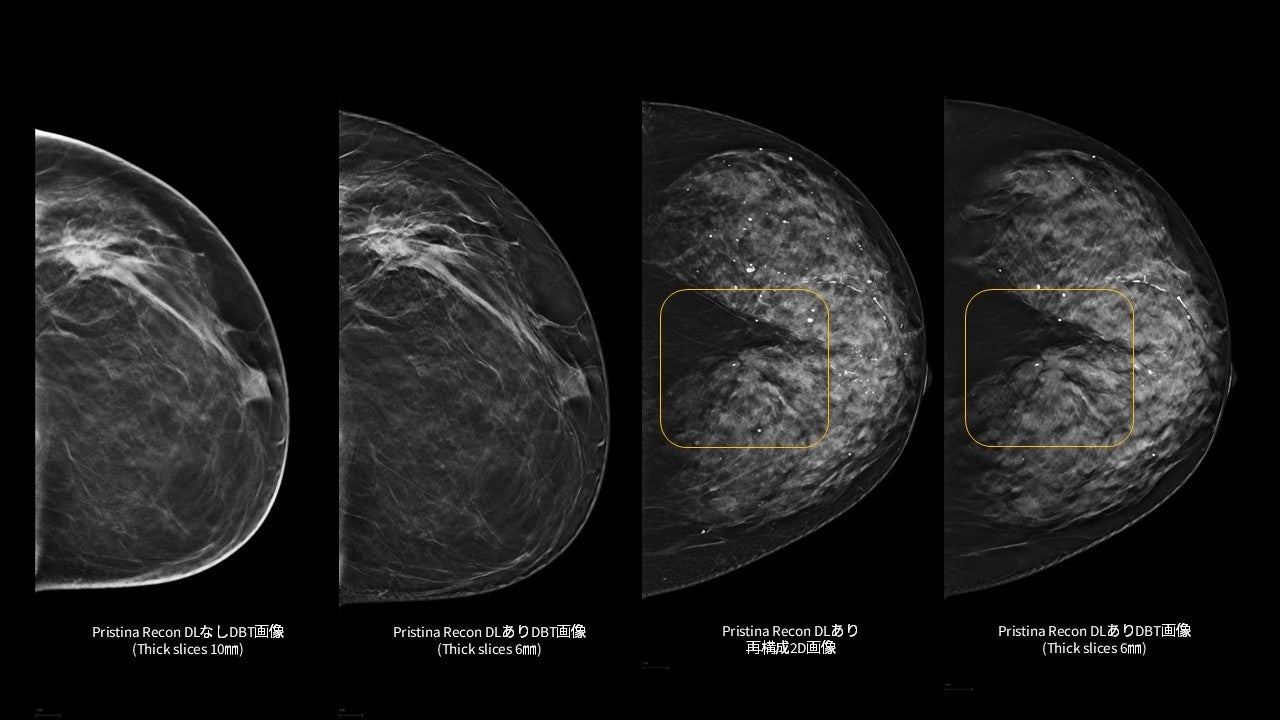

「Pristina Recon DL」¹は、MRIの画像再構成にディープラーニングを適用したGEヘルスケア独自のAIR™ Recon DL技術を基盤としています。本アプリケーションで、乳房のデジタルブレストトモシンセシス (DBT/3Dマンモグラフィ) 技術の更なる可能性を追求し、低線量での撮影でも、より高画質な画像の提供を目指します。また、アーチファクト(虚像)や視覚的ノイズの低減を図り、微細構造の視認性の向上にも寄与します。²,³

「Pristina Recon DL」は、ディープラーニングと逐次近似再構成技術を活用した、デジタルブレストトモシンセシス(DBT/3Dマンモグラフィ)向けの画像再構成技術です。また、被ばく線量を増加させることなく、高画質で安定したDBT/3Dマンモグラフィ画像の提供を目指します。

さらに、ディープラーニングを用いた高度な画像再構成技術により、アーチファクト(虚像)や視覚的ノイズを低減し、微細構造の視認性を向上させます。これにより、DBT/3Dマンモグラフィおよび再構成2D画像の双方において、読影に必要な情報をより明確に可視化し、診断を支援する読影環境の向上に貢献します。